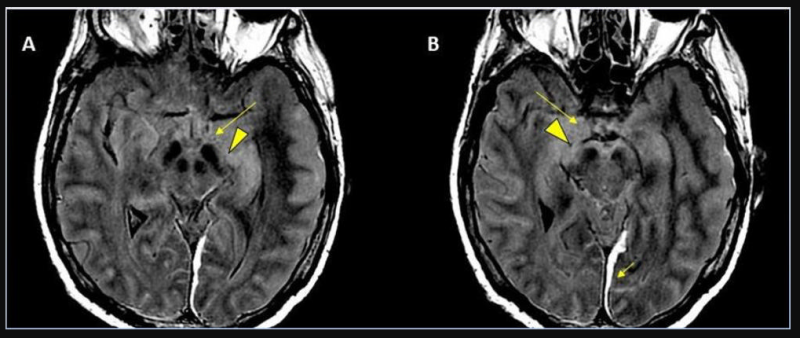

This photo gallery shows the variety of radiological presentations of COVID-19 (SARS-CoV-2) in medical imaging, including computed tomography (CT), radiograph X-rays, ultrasound, echocardiograms and magnetic resonance imaging (MRI). The radiology images show examples of typical COVID pneumonia in the lungs and the numerous complications the virus causes in the body in multiple organs, including the brain, kidneys, heart, abdomen and vascular system.